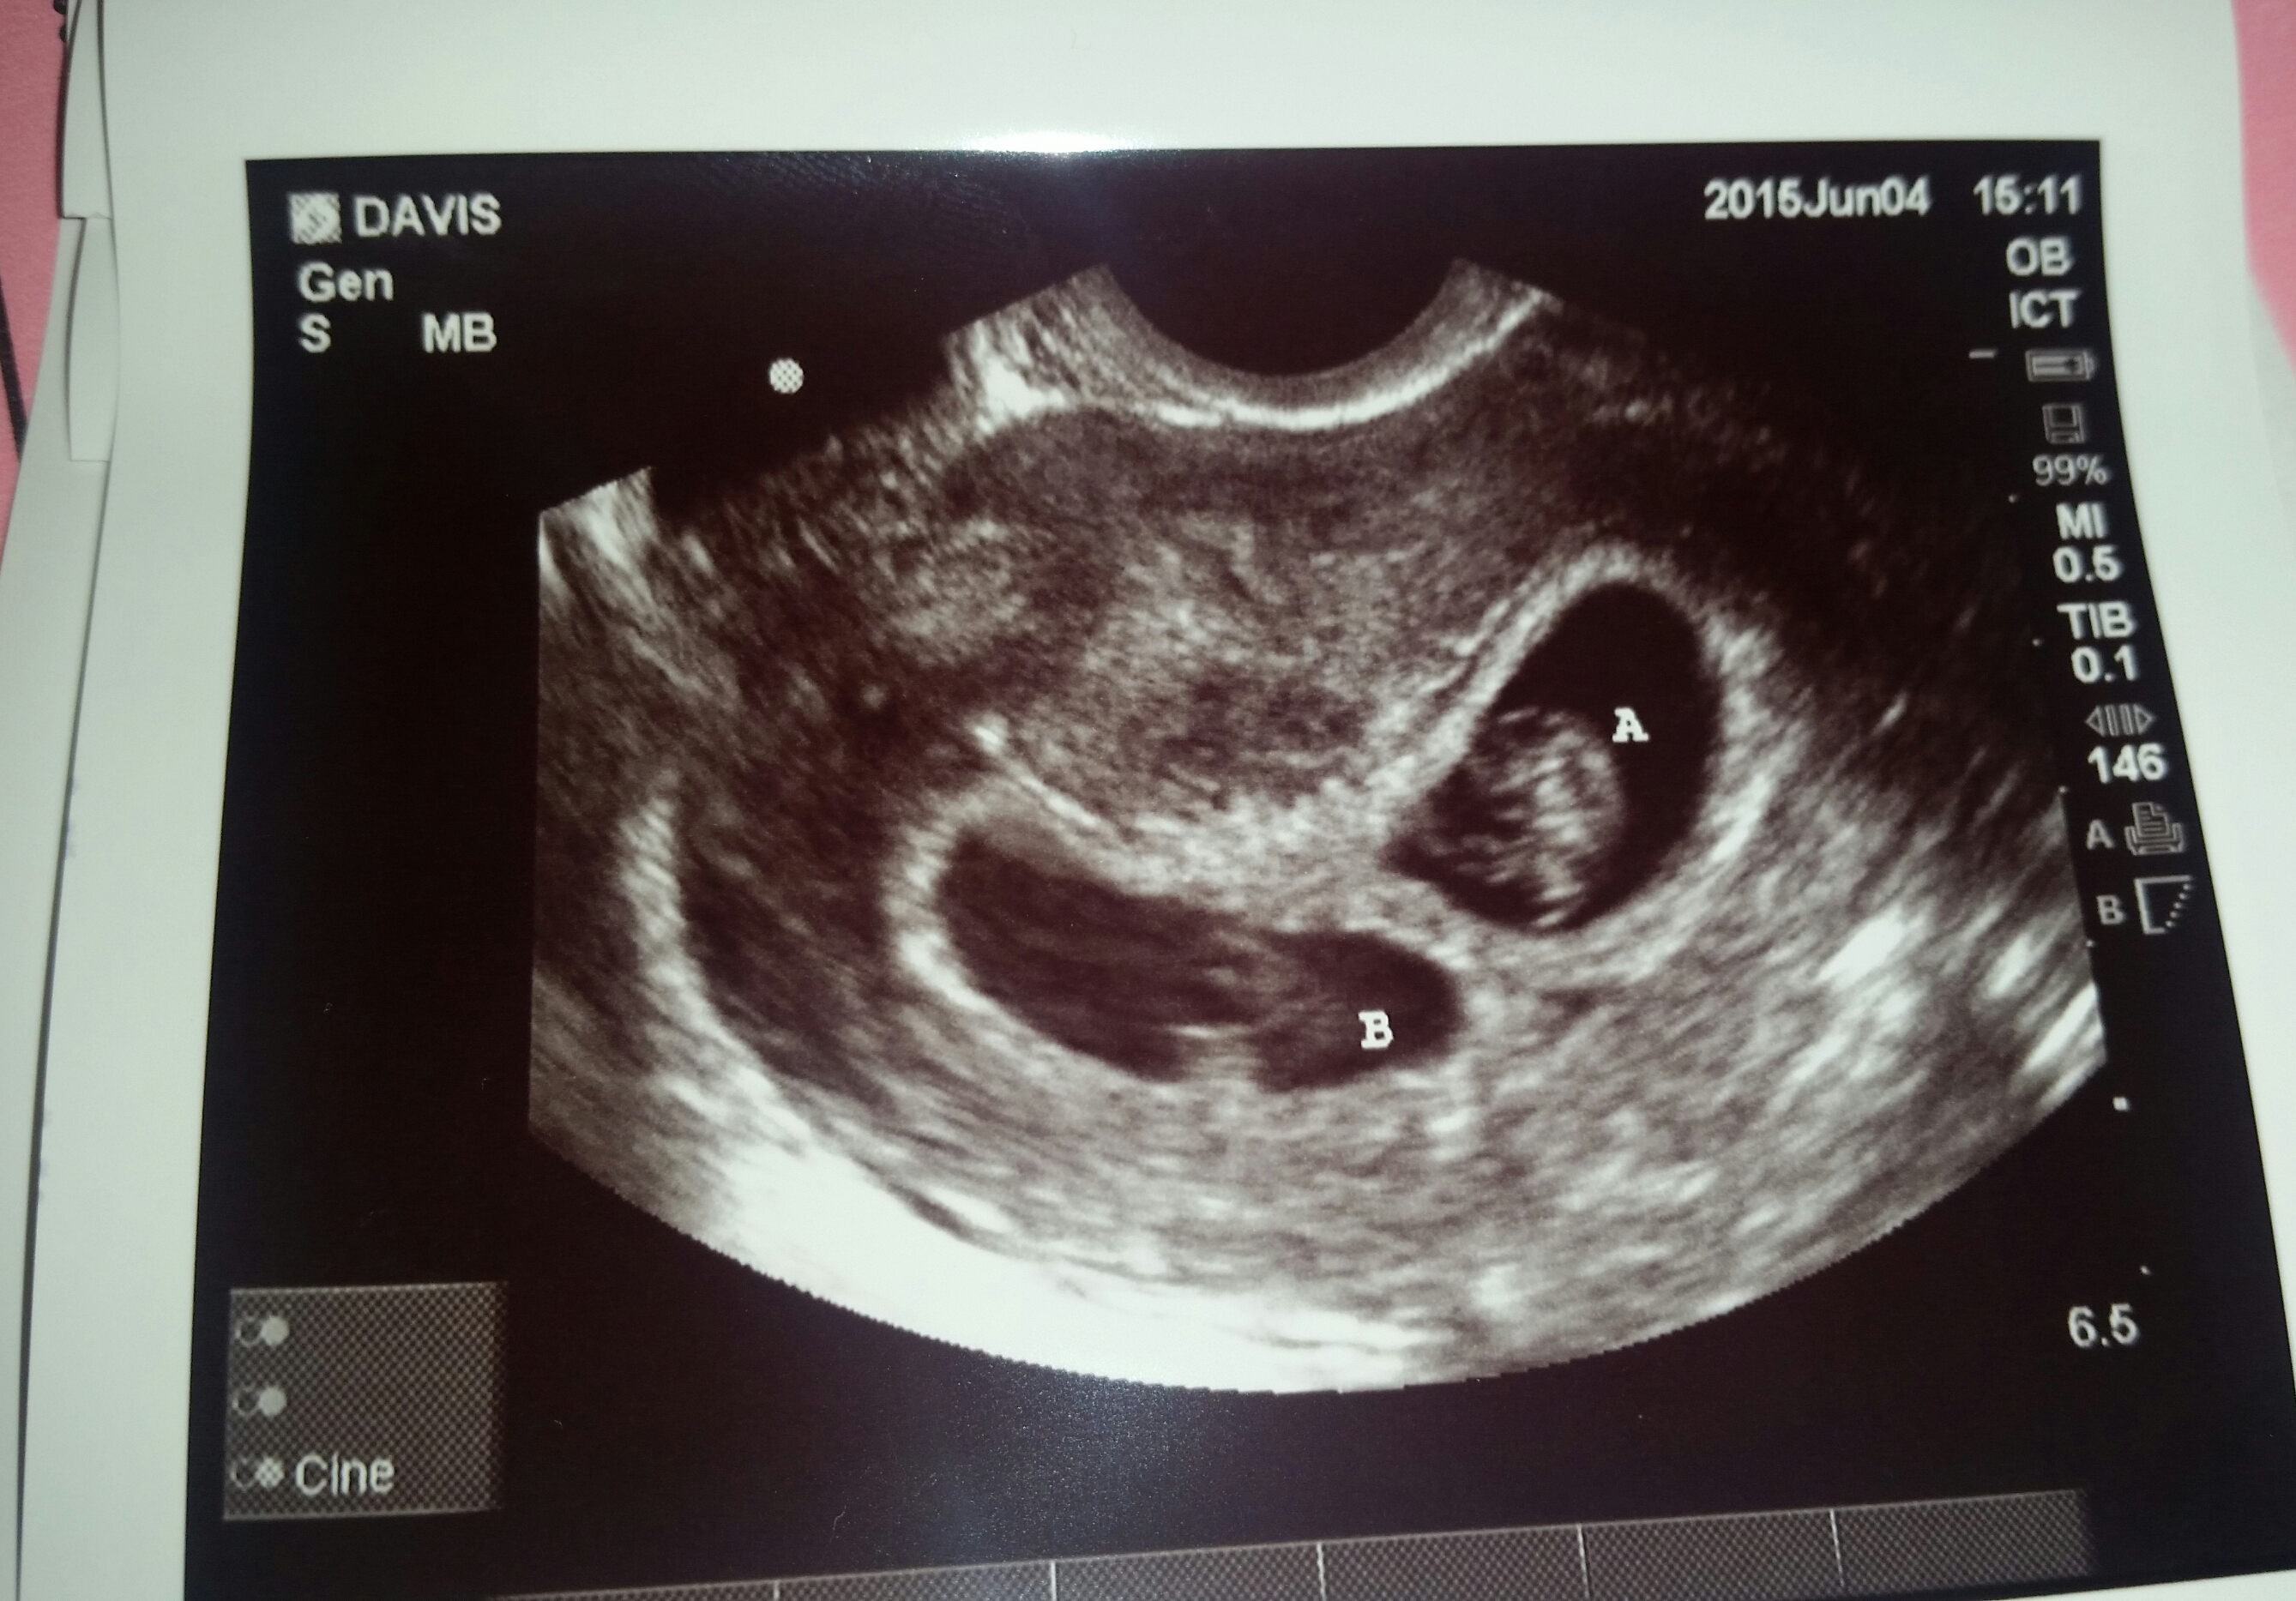

I read it is 97% accurate for singletons and not-tested in twins. In shots of my twins the ones together were at a weird angle so he could image them together and appeared diff than the ones of them separate as far as placenta placement. Does yours? I hope you have one of each that would be great!

My goodness! I have to say you two lovely ladies above this..I find it really tricky! It seems like your baby is at the bottom smack dab right in the middle!!